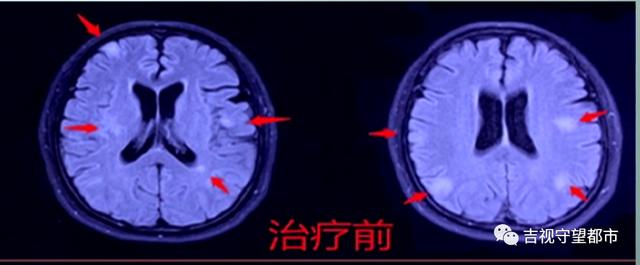

随后 , 医生建议应用抗霉菌药物 , 进行治疗 。

我们又做了清洗血的疗法 , 清除血里面的菌 , 提高免疫的方法 。

随后 , 医生建议该名患者回家口服抗霉菌药物继续治疗 , 三个月后复查 。 7月4日患者进行复查时 , 头部病灶全部消失 , 患者痊愈 。